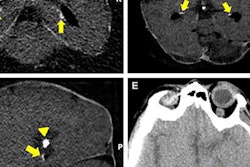

In the length method, MAC severity is determined based on the severity of calcification in a 4-cm scanned area. A MAC length of 0 cm, less than 1 cm, 1 to 2 cm, 2 to 3 cm, and greater than 3 cm on ultrasound scans correspond to MAC scores of 0, 1, 2, 3, and 4, respectively. The scores are then added up, with higher scores indicating higher MAC severity.

In the segmentation method, a point is given for the presence of any MAC in the superficial femoral artery to popliteal artery segment, the anterior tibial artery to dorsalis pedis artery segment, and the posterior tibial artery and peroneal artery segment. Like in the length method, the scores are added up, and higher scores indicate higher MAC severity.